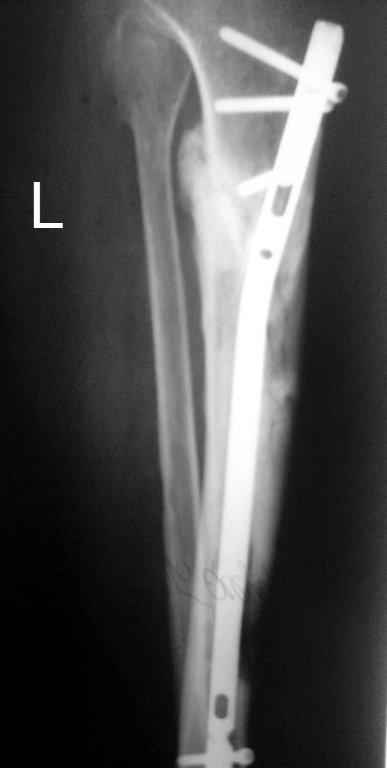

Выкладываю картинки похожей пациентки. Извините, что без окончательных снимков (сейчас их нет под рукой). Правда мы имели проблемы у данной больной после снятия аппарата, когда промежуточный фрагмент большеберцовой кости сместился на 1,5 см дистально и отошел от проксимальной части кости. До сих пор у пациентки на снимках определяется лишь тонкая полоска кости по задней поверхности за штифтом (образовалось что-то вроде маленького регенерата)в области стыковки промежуточного и проксимального фрагментов. Больная пока решила подождать. Не хочет оперироваться, так как ходит не хромая, работает.

Кратко: мужчина за 60 лет получил травму 28 лет назад (переехало автобусом). Оперировался десятки раз, в итоге с очередным патологическим переломом, хронической язвой и гипсовой лонгетой попал ко мне... Объективно - остеомиелит, инфицированный ложный сустав (или как его назвать), флегмона по наружной поверхности

голени, укорочение около 5 см.

На операции резекция 8 см, внешний остеосинтез,одновременное сближение примерно на 4 см, а затем постепенное сближение до полного контакта в течение 3 недель. Рана с патологически измененными краями, имевшая на операции размеры примерно 4-5 на 10-12 см закрылась самостоятельно в течение примерно 2-х мес. Ну не самостоятельно, конечно, а с нашей помощью, но без пластики.

Сейчас в аппарате вытянул около 6 см в верхней трети.